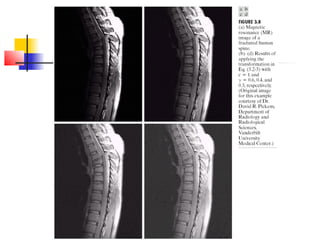

Digital Negative  Digitalnegatives are useful in the display of medical images and their processing